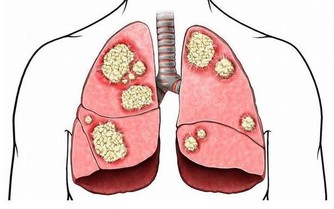

痛風,是因為人體內血液中的尿酸水平過高導致的,是尿酸鹽沉積在組織內引起的疾病。體內尿酸水平升高,主要有兩大原因,

第一就是體內產生了太多的尿酸;

第二就是排出體外的尿酸太少。

尿酸又是嘌呤代謝的產物,而人體內的嘌呤除了自身產生的之外,很重要的一個來源就是通過食物攝取。所以,如果排除了自身體質後,患痛風就要考慮平時的飲食是不是出現了問題。